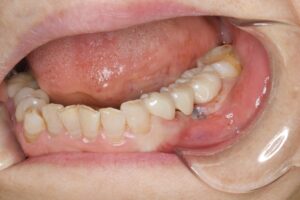

銀歯の下での虫歯の再発に対し、根管治療を歯内療法の専門医と連携しやり直し(自由診療)、その後セラミックで補綴処置を行なった。

さらに、土台を整えた後のジルコニアは、銀歯と比較して圧倒的に衛生的です。銀歯は経年劣化で変形し、セメントが溶け出した隙間から二次虫歯を招きやすいですが、ジルコニアは変質せず、汚れ(プラーク)も付着しにくい性質を持ちます。また、銀歯のように熱による膨張・収縮で歯にストレスをかけることもありません。

| 銀歯の下での虫歯の再発に対し、根管治療を歯内療法の専門医と連携しやり直し(自由診療)、その後セラミックで補綴処置を行なった。 |